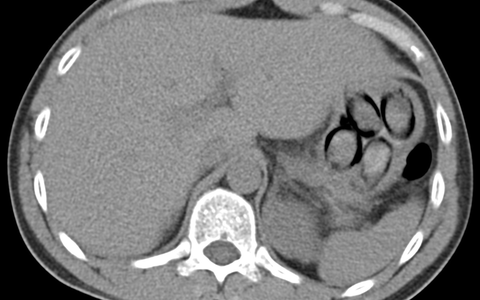

"Die Röntgenaufnahme in einem nahegelegenen Krankenhaus bestätigte letztendlich den Verdacht meiner Kolleginnen und Kollegen, denn im Magen des Mannes waren mehrere Drogenpäckchen klar zu erkennen. Insgesamt schied der Mann dann unter Überwachung sieben sogenannte Bodypacks mit insgesamt mehr als 100 Gramm Kokain aus", so Jens Ahland, Pressesprecher des Hauptzollamts Köln.